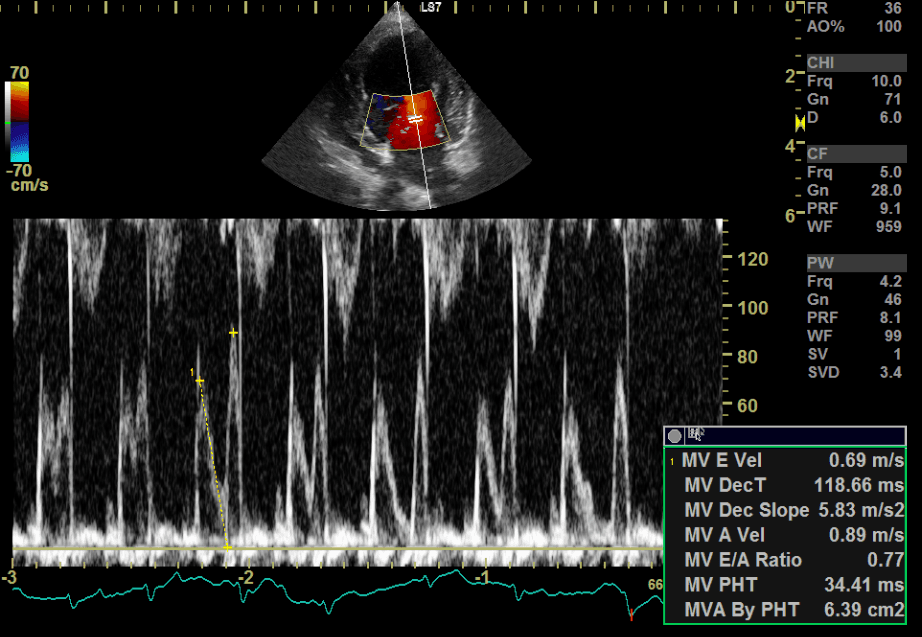

初期段階では症状がほとんど出ないため、聴診での心雑音のチェックが最初の入り口となります。聴診で心臓の雑音が確認された場合は、レントゲン検査、心臓超音波(エコー)検査、心電図、血圧測定などを行い、心臓の拡大や逆流の程度を正確に評価します。

↑色々な数値を測定して総合的に診断し、治療計画を立てます。